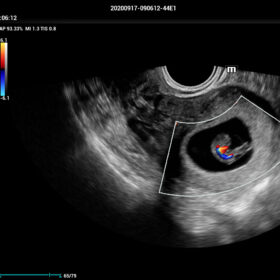

Comprehensive Imaging Solutions Powered by ZST+

The ZST+ platform is a remarkable advancement, marking a significant evolution in ultrasound technology. It revolutionizes the processing of ultrasound metrics, moving away from the traditional beam-forming approach to channel data-based processing. This breakthrough eliminates the longstanding trade-off challenges between spatial resolution, temporal resolution, and tissue uniformity. The result is outstanding image quality, providing limitless imaging solutions with continuous enhancements.

- Smart Scene 3D – Full Stack smartness obstetric solution empowered by ZST+. Comprehensive 3D/4D OB imaging solution with comprehensive fetal parts coverage.

One Key for favorite fetal part imaging, reducing manual adjustment - Smart Face – Automatic removal of occlussions over fetal face with one click

- Smart OB – Accurate auto measurements of most frequently examined parameters BPD/HC/FL/AC/OFD with a single click

- Smart FLC 2D/3D – Automatic Follicle Counting and measurements in 2D/3D mode